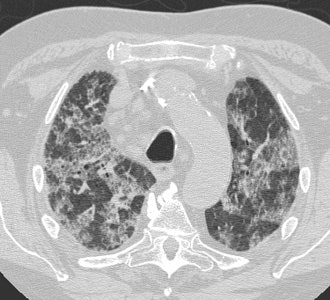

Diffuse Alveolar Damage: The patient below was admitted to the intensive care unit with increasing dyspnea. HRCT imaging revealed patchy areas of ground glass opacity and consolidation within the lungs bilaterally. There were prominent underlying reticulations within the areas of airspace disease. An open lung biopsy was performed and demonstrated diffuse alveolar damage. The etiology was not clinically apparent.  |

![]() ![]()  |